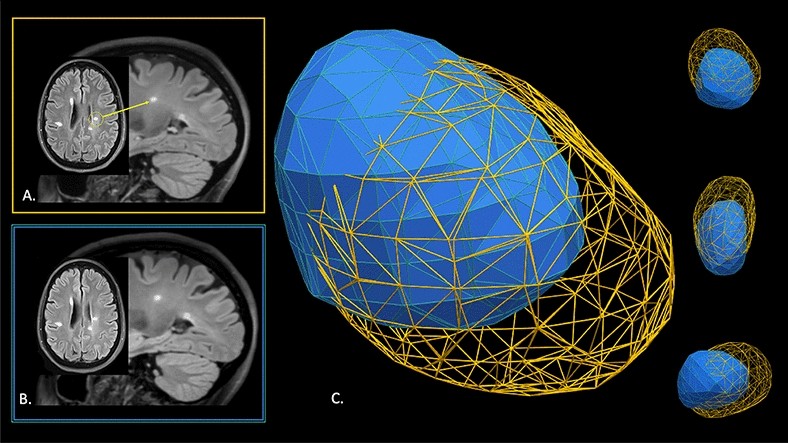

Figure 2

Two-dimensional (2D) MRI axial FLAIR and 3-dimensional (3D) sagittal FLAIR images highlighting a single MS lesion (circled in yellow) from a 49-year-old white woman with relapsing remitting disease from (A) time point 1 and (B) time point 2 (1-year follow-up). (C) Visual model in 3D demonstrating displacement and deformation of the lesion at time point 2 (blue) compared to the original position at time point 1 (yellow mesh). Note both the reduction in size and positioning of the lesion between time points that is not apparent on review of the longitudinal 2D MRI data (A,B).